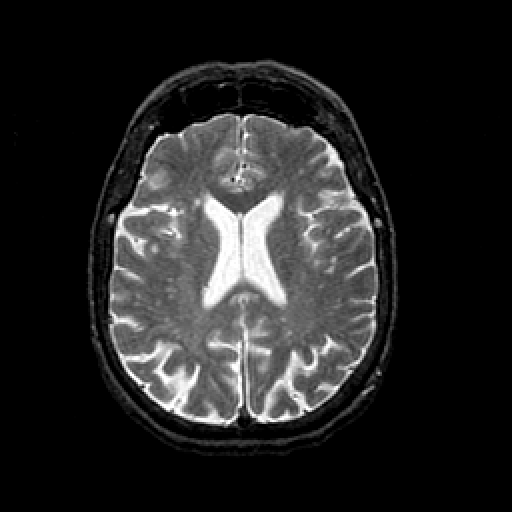

T2-weighted structural MR: Slice 33

Slice 33